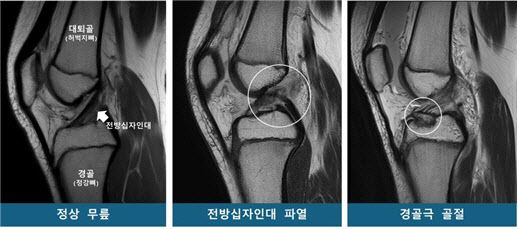

소아청소년은 뼈와 근육 발달이 미성숙해 스포츠 손상에 취약하다. 특히 ‘전방십자인대 파열’과 ‘경골극 골절’은 소아청소년에게 발생하기 쉬운 대표적인 무릎 손상이다. 같은 외상을 입어도 어떤 환자는 십자인대가 파열되고, 다른 환자는 경골극 골절이 발생하는데, 이처럼 서로 다른 손상이 발생하는 원인은 명확치 않다.

연구팀은 소아청소년을 53명씩 ▲전방십자인대 파열군 ▲경골극 골절군 ▲대조군(정상 무릎)으로 구분하고 연령·성별을 매칭했다. 이후 MRI를 재구성한 3차원 영상을 바탕으로 14개의 해부학적 지표를 분석했다.

그 결과, 두 무릎 손상군은 대조군보다 ‘경골 바깥쪽 관절면 경사’가 유의미하게 높았다. 통계 분석에 따르면 경사가 높을수록 전방십자인대 파열 및 경골극 골절 발생 위험이 각각 1.42배, 1.33배 증가해, 이 값이 소아청소년의 주요 무릎 손상에 대한 위험인자로 확인됐다. 반면, ‘대퇴과간 절흔 폭(무릎뼈 사이 공간)’은 전방십자인대 파열군에서만 유의미한 연관성이 있었다. 특히 이 폭이 넓을수록 파열 위험이 감소하는 보호 효과가 확인됐다.

연구팀은 경골 바깥쪽 관절면의 경사가 가파를수록 무릎에 무게가 실릴 때 대퇴골(허벅지뼈)이 바깥쪽으로 회전하며, 그 결과 전방십자인대가 과부하되어 파열이나 경골극 골절로 이어질 수 있다고 설명했다. 또한 대퇴과간 절흔 폭이 넓을 경우, 전방십자인대가 대퇴골과 덜 충돌하기 때문에 파열 위험이 낮아지는 경향이 있다고 밝혔다.